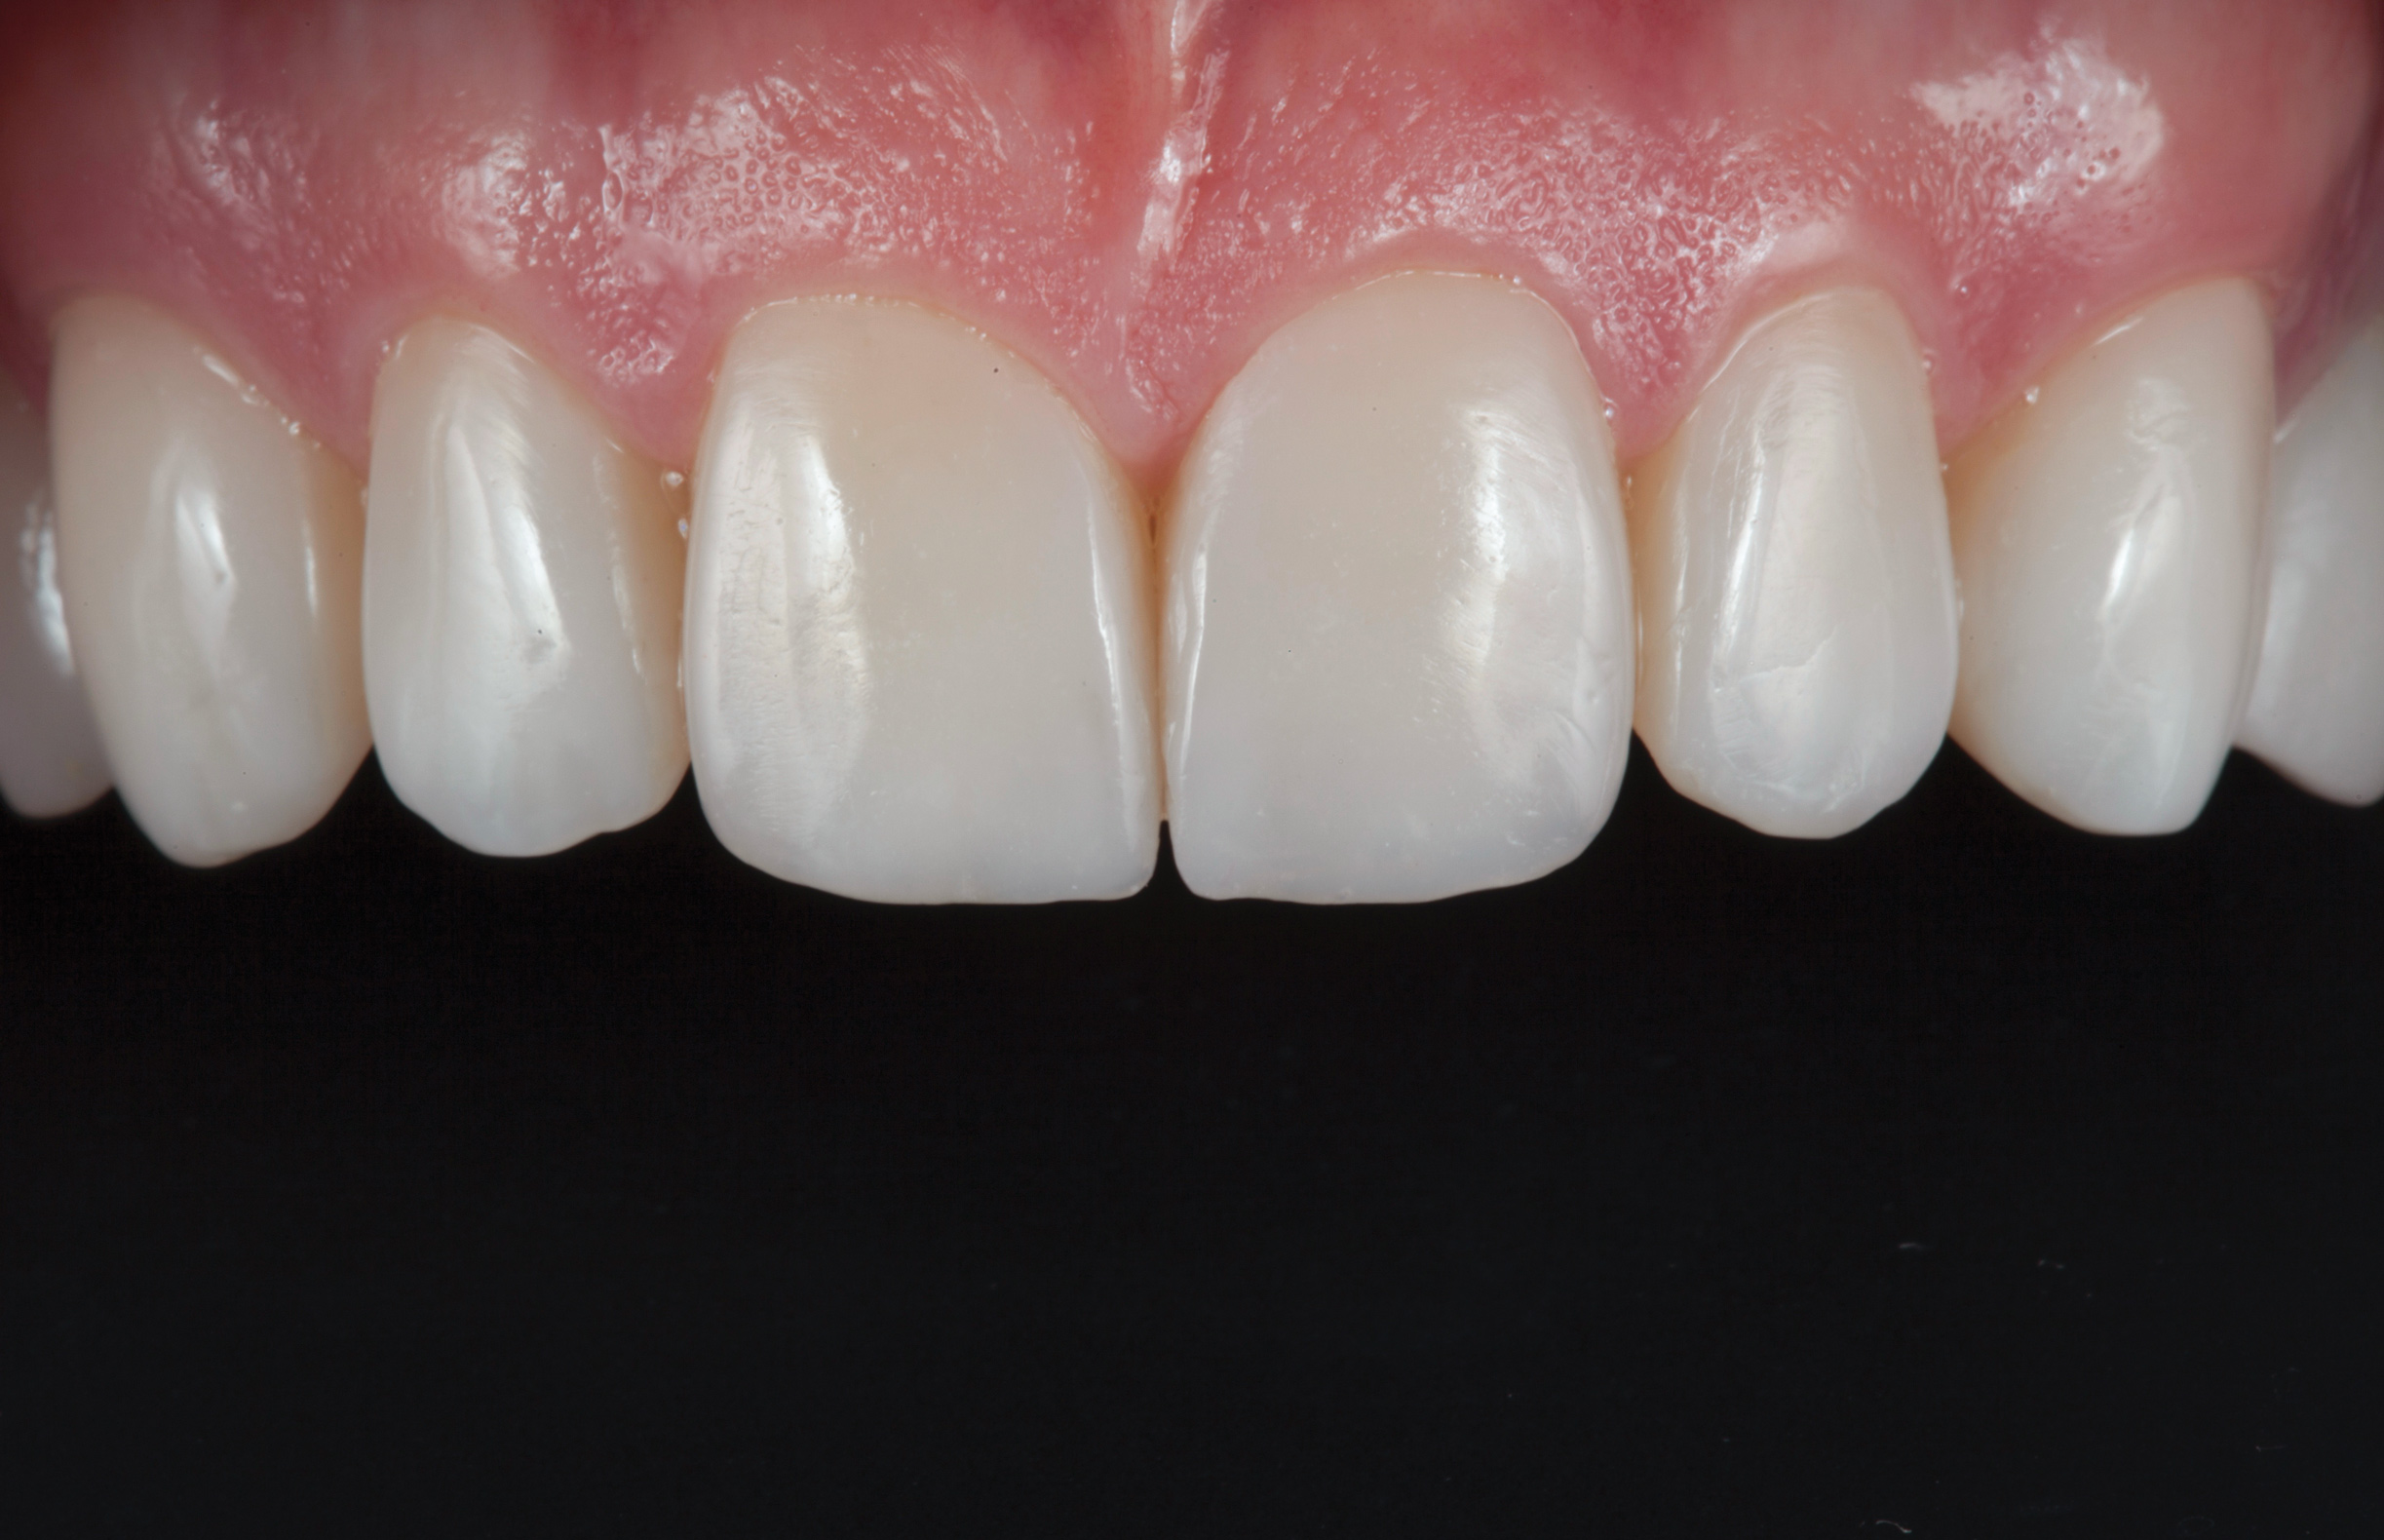

(1.) Preoperative smile photograph.

Figure 1

A 34-year-old male patient with no medical issues presented to the office with the chief complaint of a failing crown on tooth No. 12. The patient was also unhappy with his bite and the appearance of his teeth (Figure 1 and Figure 2).

The dentofacial examination revealed a low smile line with no incisor display when the lips were in repose. The anterior teeth were chipped and worn, and their overall color was darkened. The buccal corridors were deficient, and the failing crown on tooth No. 12 was visible in a full smile.

(10.) Postoperative smile photograph.

Figure 10